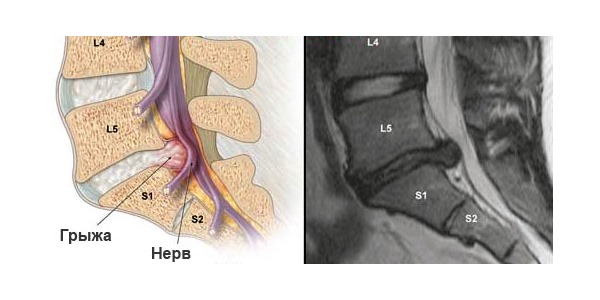

Врачи отмечают, что боли в пояснице у мужчин могут быть вызваны различными факторами. Одной из основных причин является неправильная осанка и малоподвижный образ жизни, что приводит к перенапряжению мышц и дискомфорту. Также часто встречаются травмы, связанные с физической активностью, а также заболевания, такие как остеохондроз или межпозвоночная грыжа.

Одной из наиболее распространенных причин болей в области поясницы является межпозвоночная грыжа.

Кроме того, любые дегенеративные изменения в позвоночнике могут стать источником болевого синдрома в поясничной зоне.

| Межпозвоночная грыжа | Острая, стреляющая боль, часто иррадиирующая в ногу (радикулит), онемение, слабость в конечности. Усиливается при кашле, чихании. | Покой, НПВС, миорелаксанты, физиотерапия, эпидуральные инъекции, в тяжелых случаях – хирургическое вмешательство. |